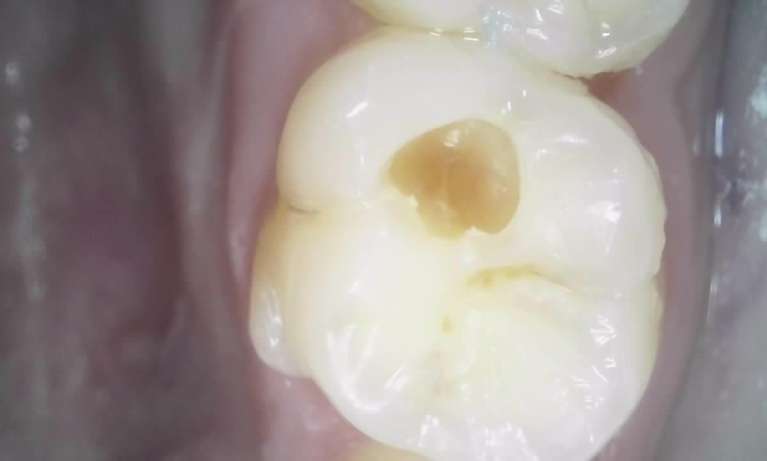

We take great pride in the services we perform in our office. We always try to not only meet your expectations, but we also try to exceed them. There are many types of services that we perform in our office, as well as others that we perform in coordination with highly skilled specialists. We have compiled a few examples of the treatments that we have performed. We are proud to say that these are the usual results our patients expect to see.

The photos are not retouched, nor are they taken by a professional photographer. These are just the routine treatment photos that we take and the results that we see every day. They are by no means a comprehensive catalog of the procedures that we perform. They are just a small sample of some of the results you can expect when you seek treatment in our office.